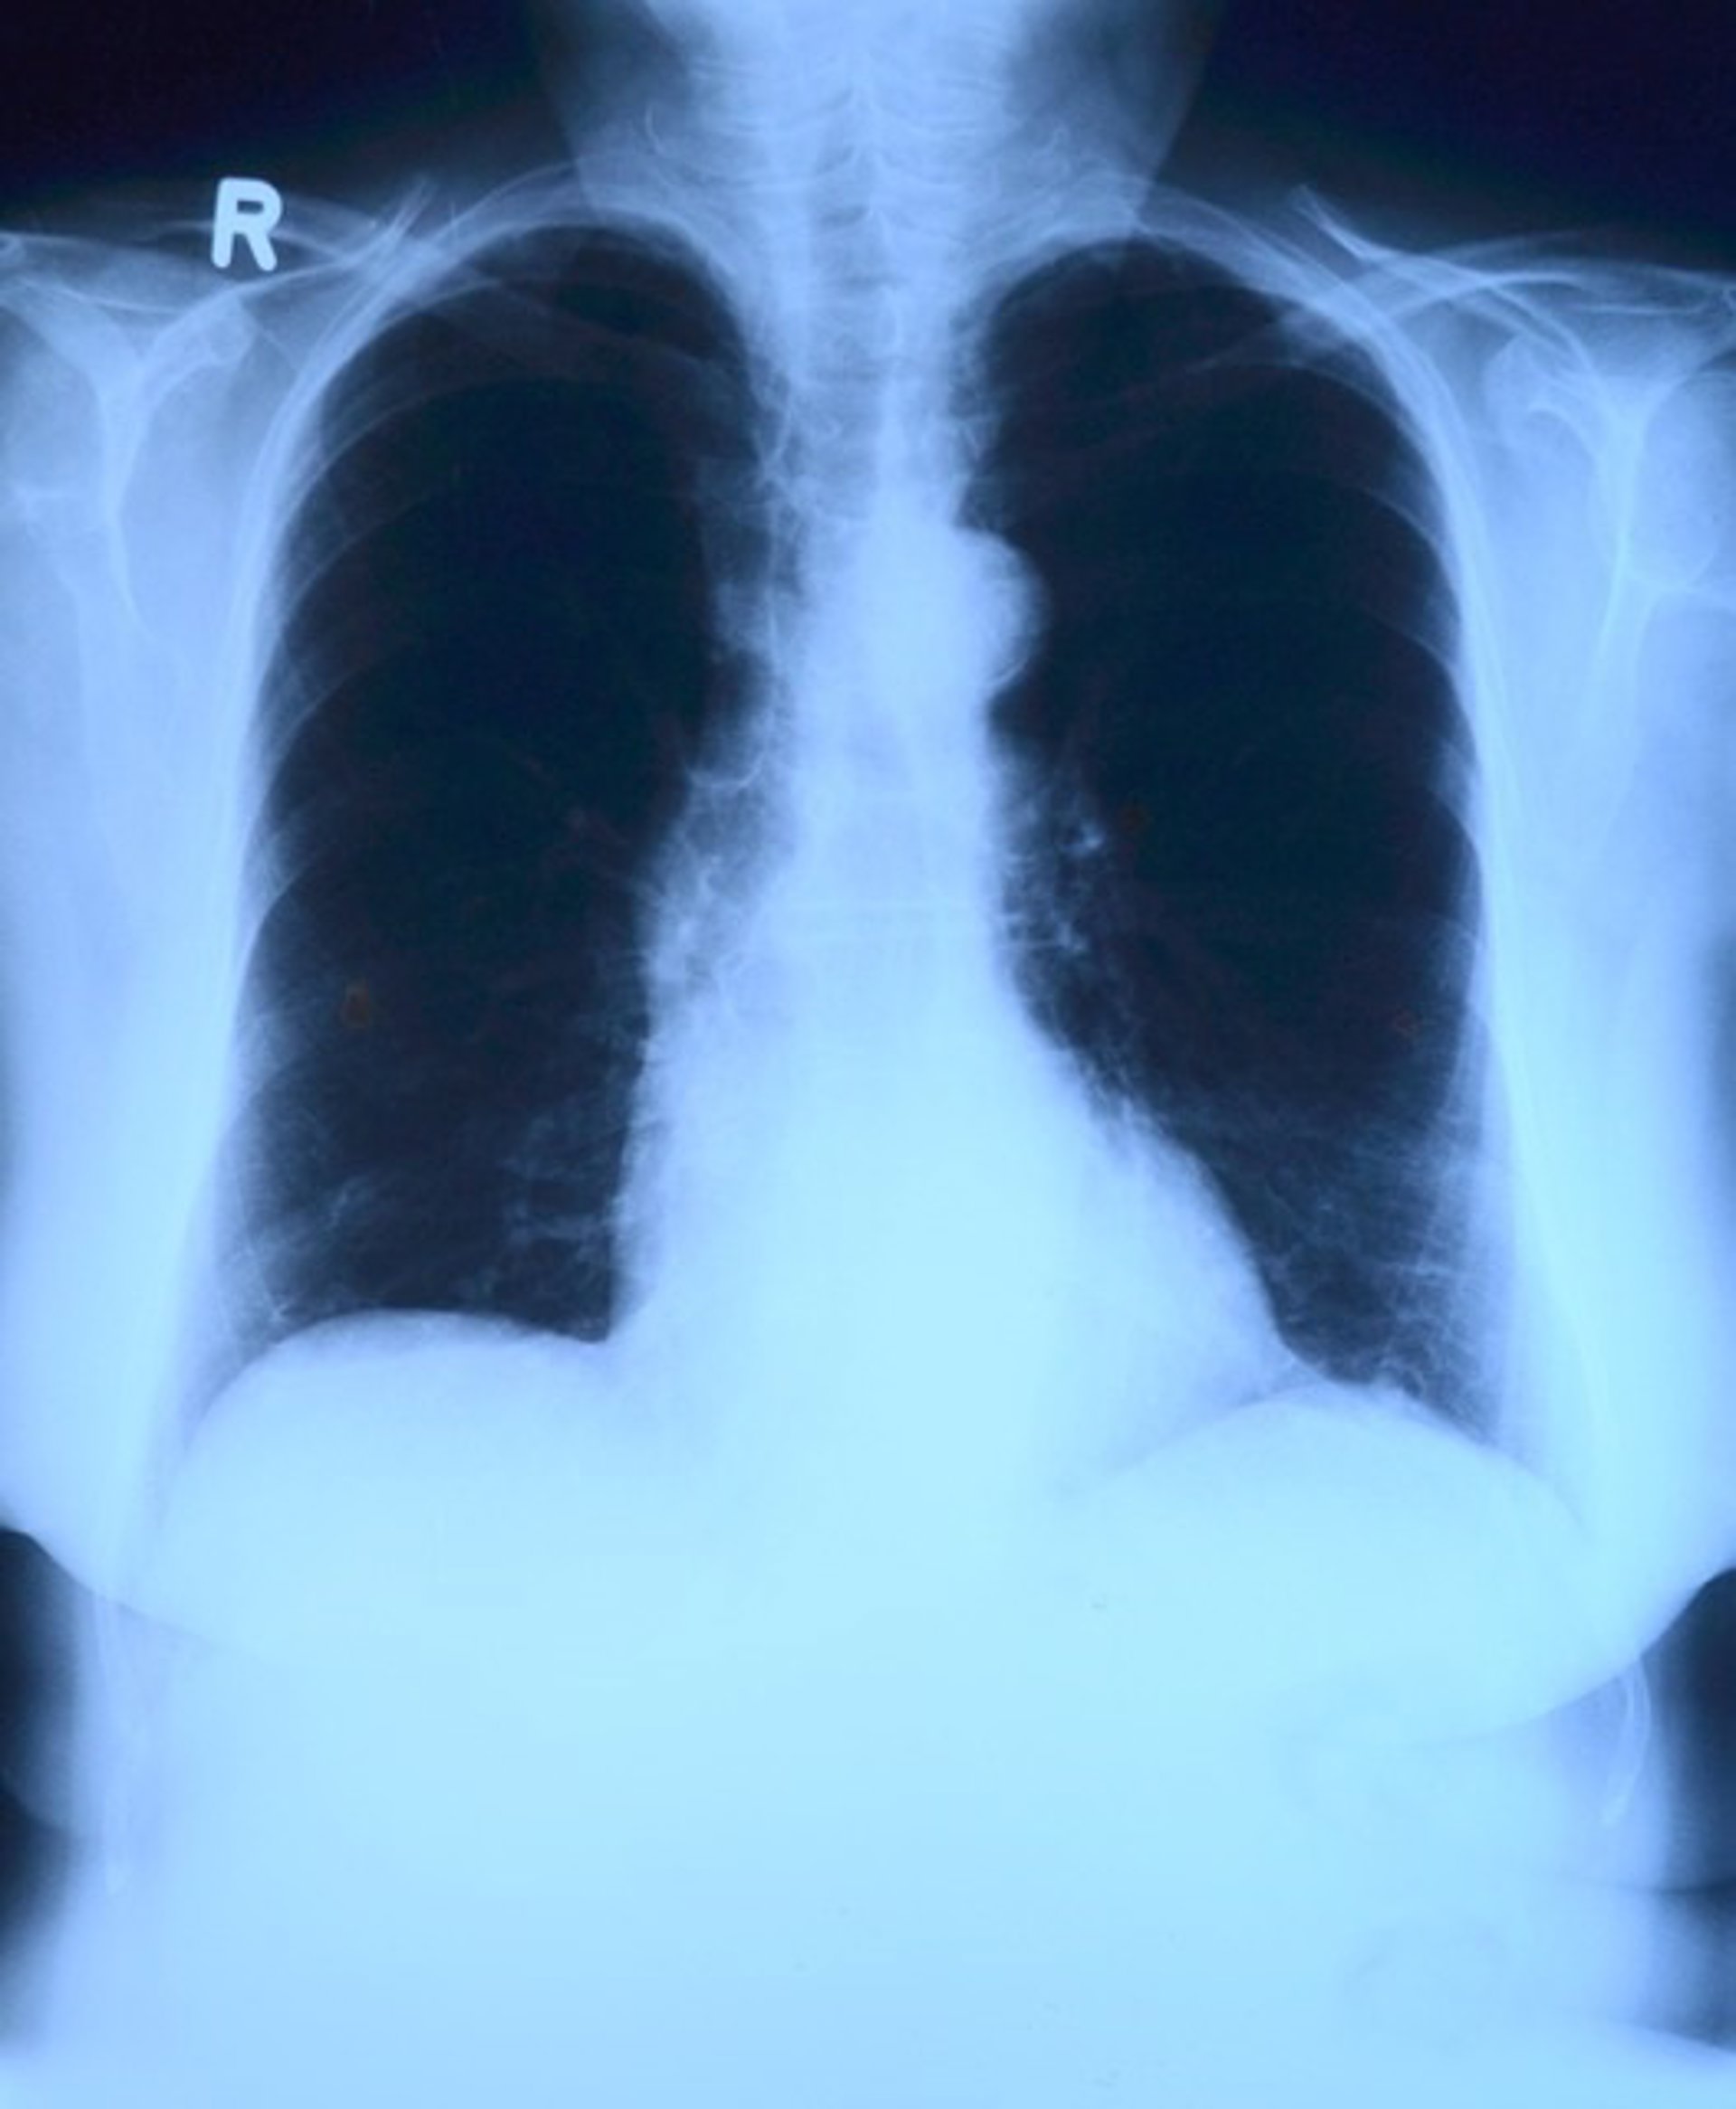

Una nueva investigación, mediante células madre magnetizadas ha sido probada con éxito en ratones para tratar la silicosis, una enfermedad pulmonar ocupacional que padecen millones de trabajadores en todo el mundo, y que puede causar la muerte sin que en la actualidad exista una cura, según publican sus autoras en la revista 'STEM CELLS Translational Medicine' ( SCTM ).

La silicosis es el resultado de años de inhalar micropartículas de polvo de sílice por parte de trabajadores en profesiones como la construcción y la limpieza con chorro de arena. Las partículas pueden provocar inflamación y cicatrización del tejido pulmonar, lo que a su vez dificulta la respiración y puede provocar la muerte.